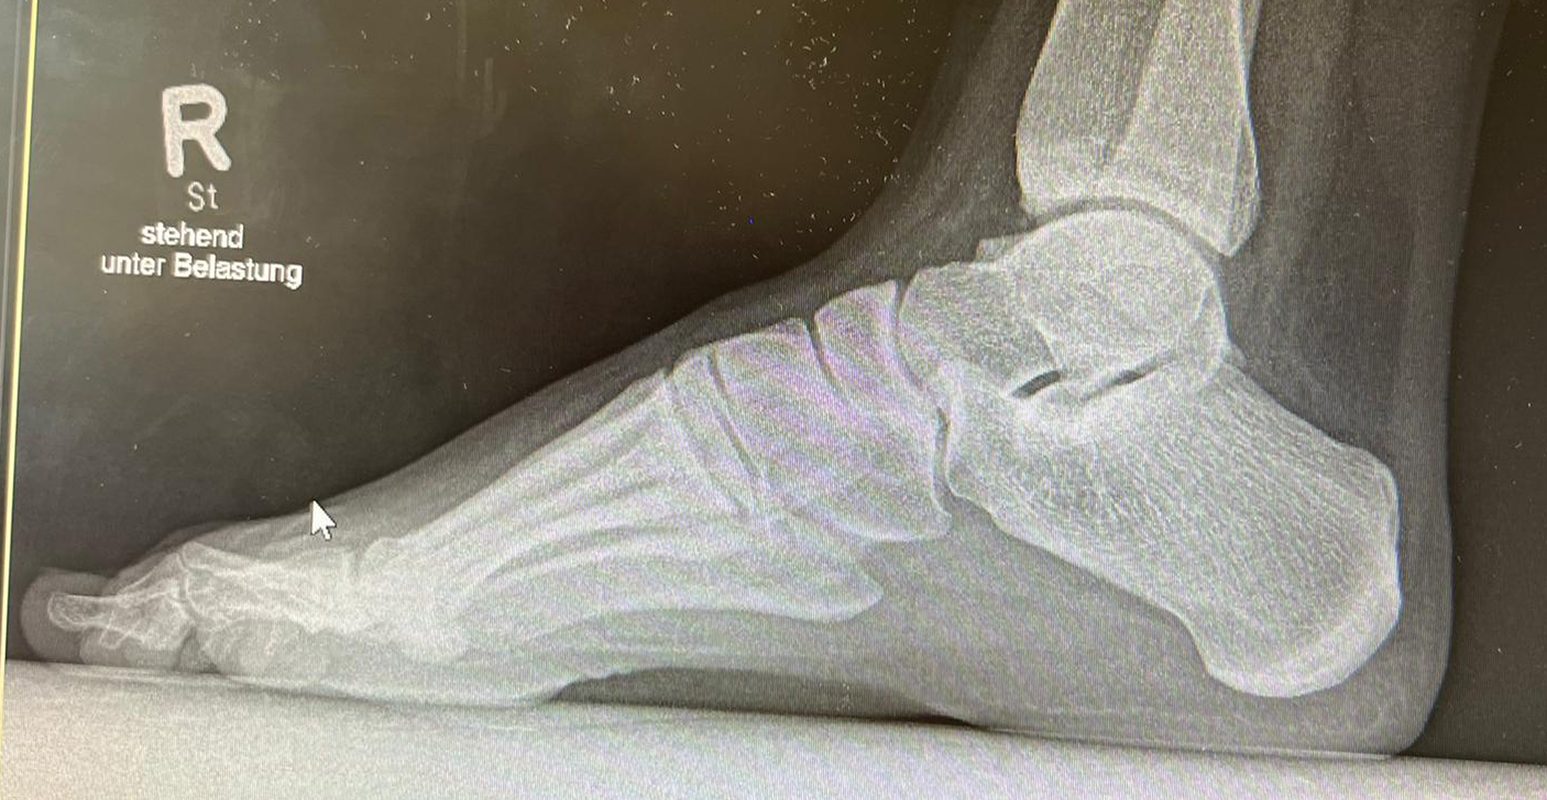

Diagnostisches Vorgehen

Damit die minimalinvasive Fußchirurgie zur Korrektur kindlicher oder jugendlicher Fußdeformitäten erfolgreich angewendet werden kann, erfordert die präoperative Diagnostik Röntgenbilder in drei Ebenen am stehenden Fuß. Röntgenbilder ohne Belastung des Fußes sind nicht zielführend. Im Fall von schweren Rückfußdeformitäten wird das obere Sprunggelenk in die radiologische Diagnostik mit einbezogen in Kombination mit der Rückfußaufnahme unter Belastung („Saltzman View“). Das OSG wird in zwei Ebenen geröntgt. Die streng seitliche Aufnahme des OSG kann bei den komplexen Fußdeformitäten mit der seitlichen Aufnahme des Fußes unter Belastung kombiniert werden. Das reduziert die diagnostische Strahlenbelastung der Kinder.

Indikationen für die beschriebenen Röntgenaufnahmen sind Klumpfußdeformitäten zur Beurteilung eines „flat top talus“ oder neurologische Grunderkrankungen mit varischer Fersenstellung wie zum Beispiel bei HSMN (Hereditäre Sensorische Motorische Neuropathie).